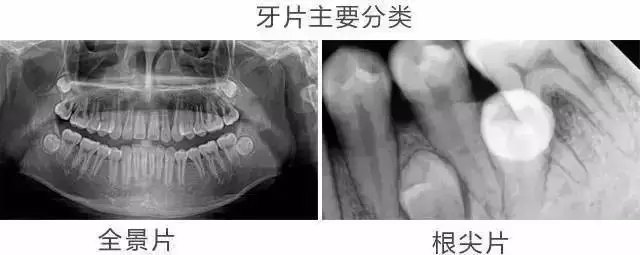

不過比較常見的牙片一般有CT片(包括全頜片、全顱片),以及根尖片,還有全景片以及側(ce) 位片等,根尖片價(jia) 格比較低,幾十元就可以,全景片和側(ce) 位片一般在一兩(liang) 百元。就是CT片稍微貴一兩(liang) 百元。而幾百元是目前大家基本都能消費得起的。

而做口腔檢查拍牙片是為(wei) 了更好的了解牙齒具體(ti) 情況,比如說智齒是需要拍全景片的,做根管治療通常需要拍根尖片,一般需要根據不同的牙齒情況來確定要做哪些檢查,而且有的可能是需要做幾個(ge) 檢查,這都是可能的,所以價(jia) 格會(hui) 有差異,這是很正常的。